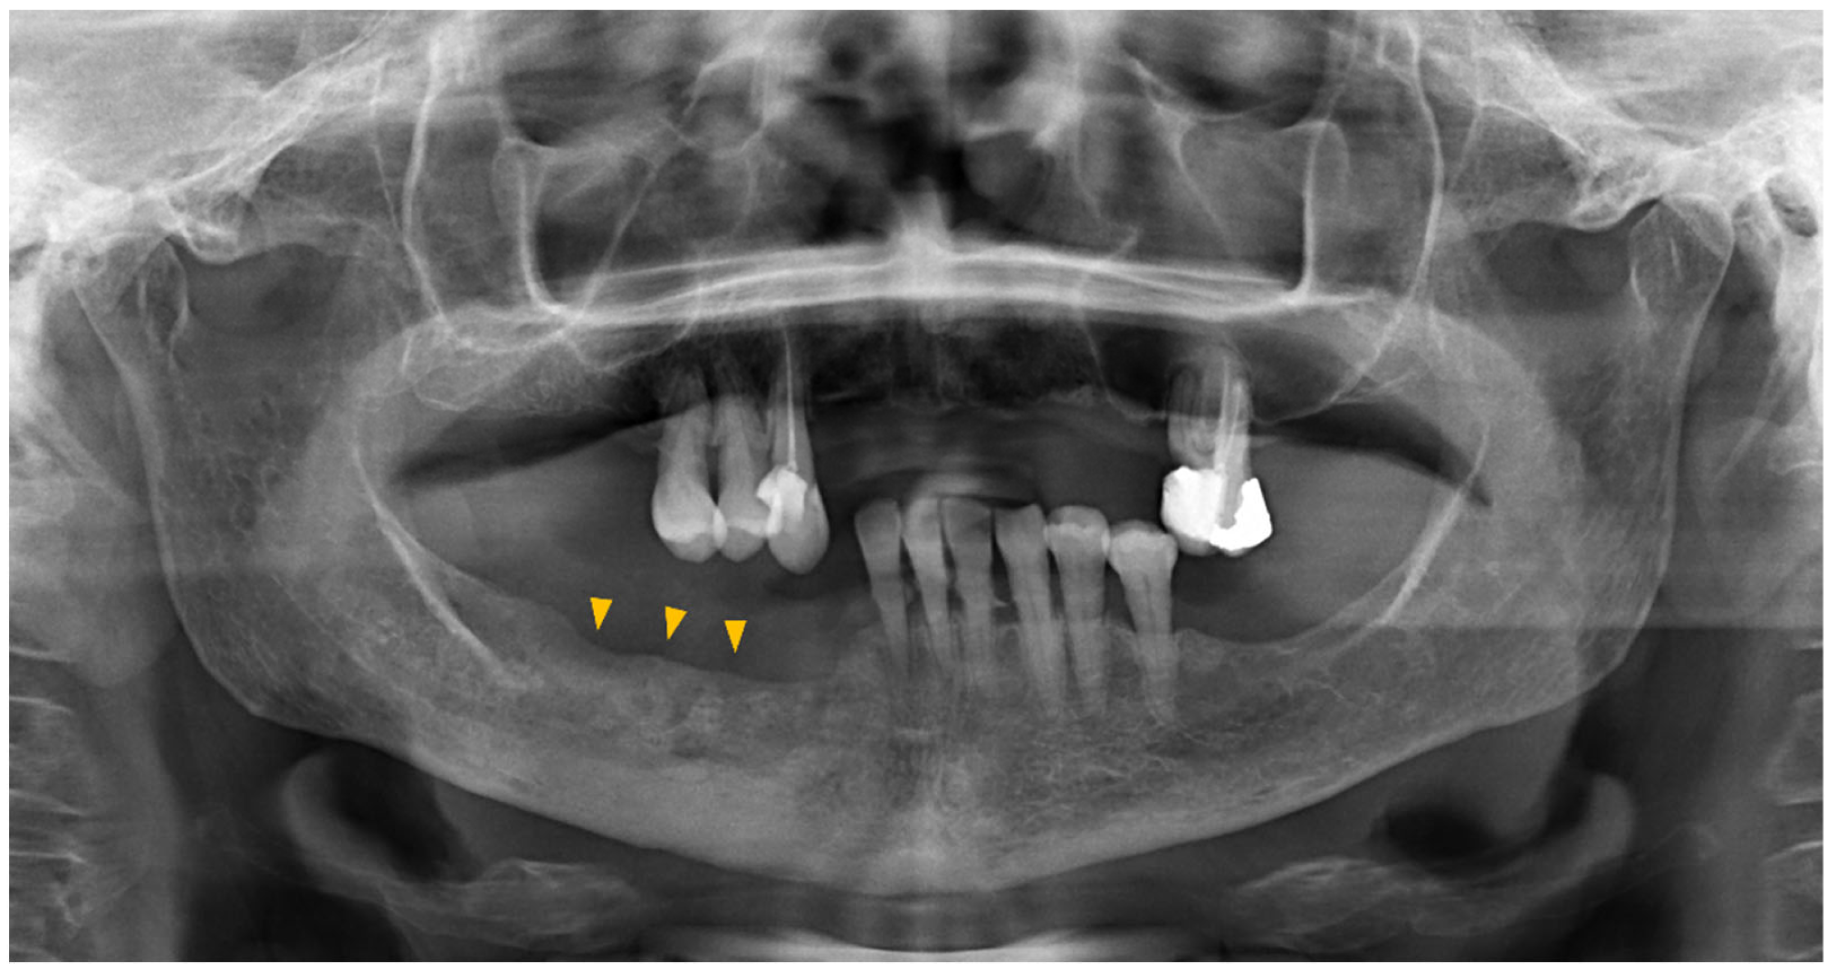

| Early | Bone cortical erosion |

| Thickening of alveolar crest and lamina dura | |

| Thickening of the trabecular bone | |

| Focal medullary osteonecrosis | |

| Persistance of the post-extraction socket | |

| Widening of the periodontal space | |

| Tardive | Oro-antral, oro-nasal, or oro-cutaneous fistula |

| Phatological fracture | |

| Thickening of the inferior alveolar canal | |

| Extended osteolysis of the maxillary sinus | |

| Diffused osteosclerosis of the jaws | |

| Osteosclerosis of the zygoma and/or hard palate | |

| Periosteal reaction | |

| Sinusitis |